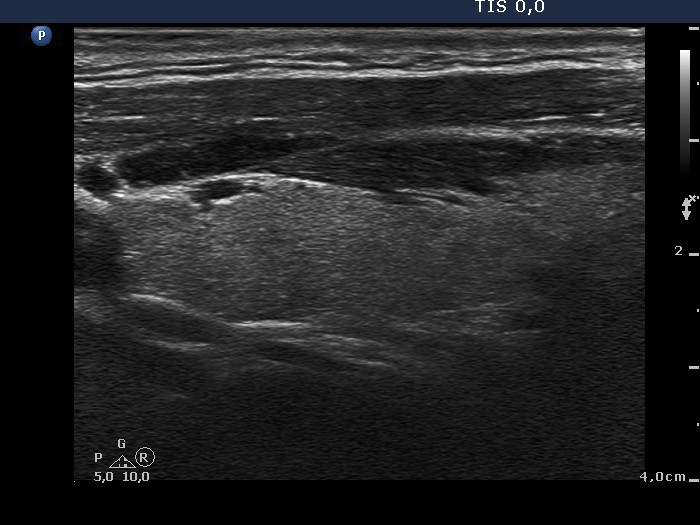

Teamwork - case conp 052 (ultrasonographic picture 2)

Right lobe, longitudinal scan.